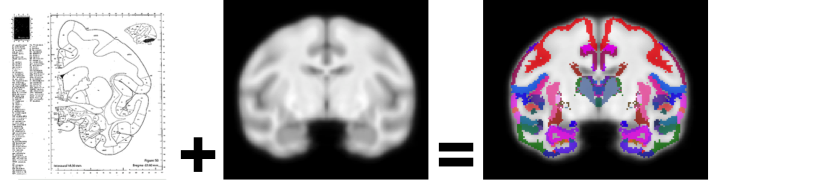

Wisconsin Rhesus Brain Parcellation

Wisconsin Rhesus Brain Parcellation Images

Description:Graphical Abstract